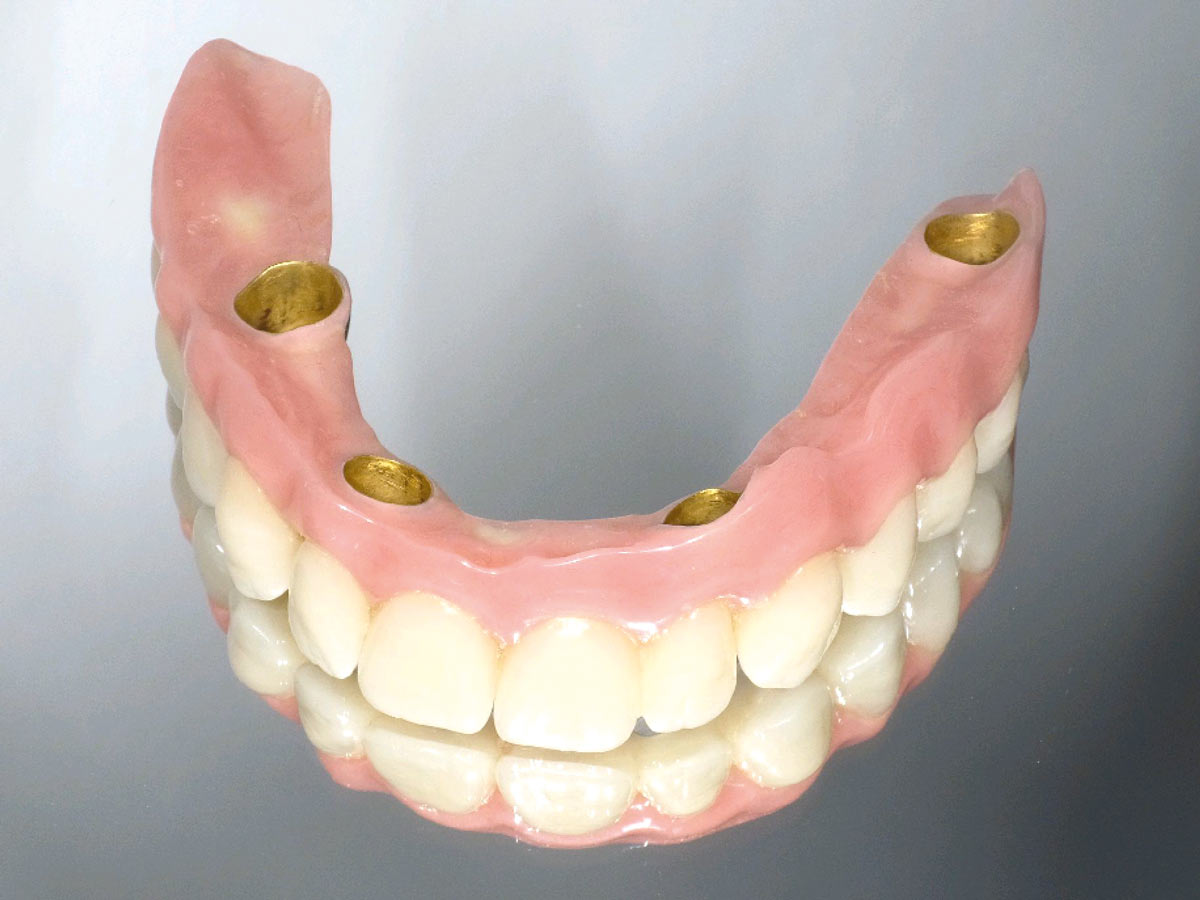

21/23 - Telescopic prosthesis

Full arch reconstruction of the maxilla with maxgraft® bonebuilder - Dr. M. Erbshäuser